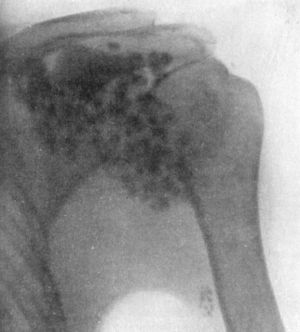

| 104. | Radiogram of Specimen of Arthropathy of Shoulder in Syringomyelia | 204 |

| 105. | Radiogram showing Multiple partially Ossified Cartilaginous Loose Bodies in Shoulder-joint | 205 |